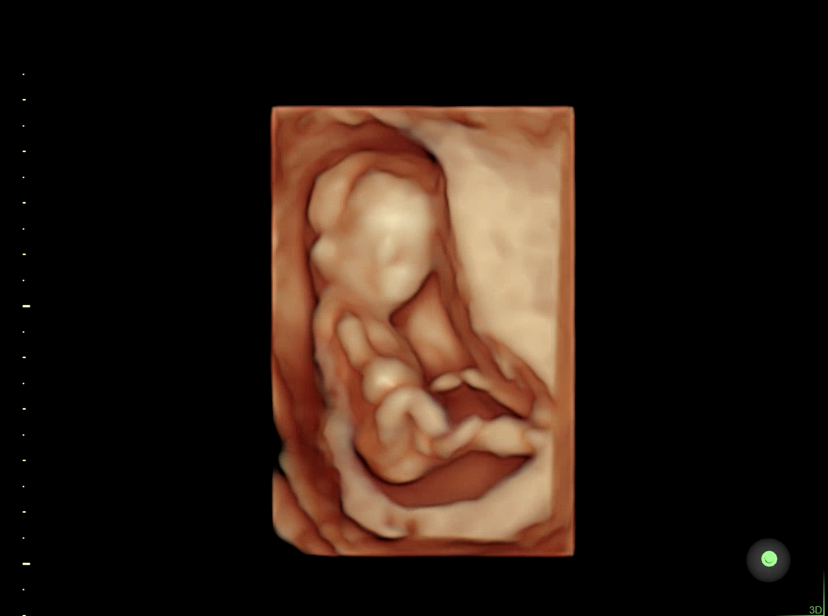

12주차 / 16주차 / 24주차(머리가 낑겨서 좀 좁아보임)